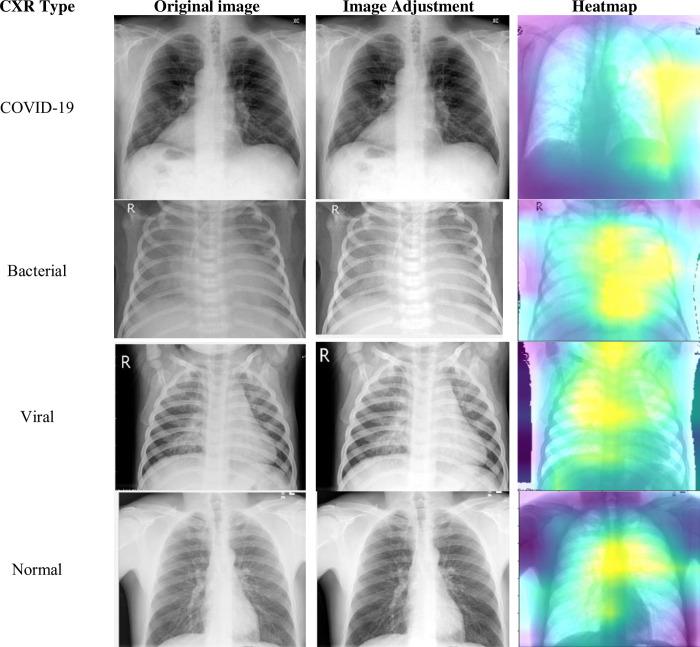

Deep learning and artificial intelligence offer promising tools for improving the accuracy and efficiency of diagnosing various lung conditions using portable chest x-rays (CXRs). This study explores this potential by leveraging a large dataset containing over 6,000 CXR images from publicly available sources. These images encompass COVID-19 cases, normal cases, and patients with viral or bacterial pneumonia. The research proposes a novel approach called "Enhancing COVID Prediction with ESN-MDFS" that utilizes a combination of an Extreme Smart Network (ESN) and a Mean Dropout Feature Selection Technique (MDFS). This study aimed to enhance multi-class lung condition detection in portable chest X-rays by combining static texture features with dynamic deep learning features extracted from a pre-trained VGG-16 model. To optimize performance, preprocessing, data imbalance, and hyperparameter tuning were meticulously addressed. The proposed ESN-MDFS model achieved a peak accuracy of 96.18% with an AUC of 1.00 in a six-fold cross-validation. Our findings demonstrate the model's superior ability to differentiate between COVID-19, bacterial pneumonia, viral pneumonia, and normal conditions, promising significant advancements in diagnostic accuracy and efficiency.

深度学习和人工智能为利用便携式胸部 X 光(CXR)提高诊断各种肺部疾病的准确性和效率提供了有前途的工具。本研究通过利用包含来自公开来源的超过 6000 张 CXR 图像的大型数据集来探索这种潜力。这些图像包括 COVID-19 病例、正常病例以及患有病毒性或细菌性肺炎的患者。该研究提出了一种名为“利用 ESN-MDFS 增强 COVID 预测”的新方法,该方法结合了极端智能网络(ESN)和平均辍学特征选择技术(MDFS)。本研究旨在通过将静态纹理特征与从预训练的 VGG-16 模型提取的动态深度学习特征相结合,提高便携式胸部 X 光片中多类肺部疾病的检测能力。为了优化性能,对预处理、数据不平衡和超参数调整进行了细致的处理。在六重交叉验证中,所提出的 ESN-MDFS 模型的峰值准确率达到 96.18%,AUC 为 1.00。我们的研究结果表明,该模型在区分 COVID-19、细菌性肺炎、病毒性肺炎和正常情况方面具有卓越的能力,有望在诊断准确性和效率方面取得重大进展。